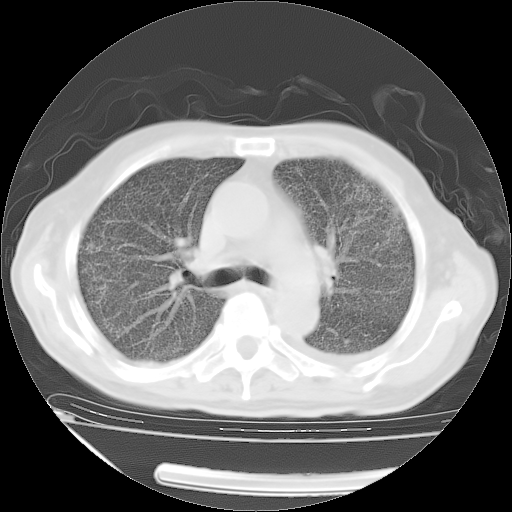

甲强龙80mg/日+抗结核治疗(异烟肼+利福霉素+乙胺丁醇)10天。复查肺部CT。

治疗10天肺部CT